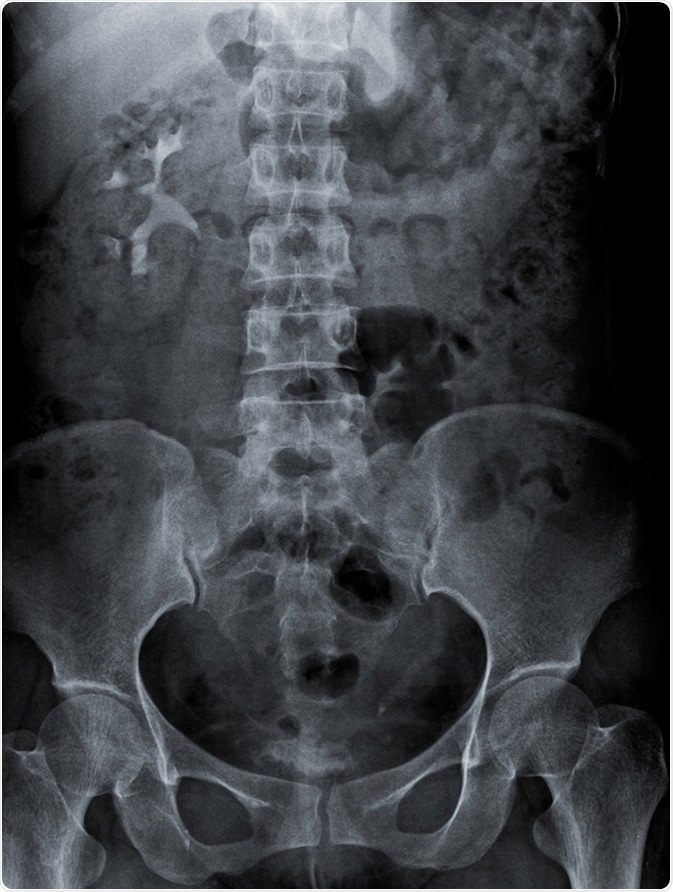

Radiography of kidney with intravenous Contrast at one hour. Image Credit: kaling2100 / Shutterstock

The region covered by a KUB radiograph includes the area that spans the superior poles of the kidneys downwards to the pubic symphysis. This radiograph, like all X-rays, employs the use of external electromagnetic beams to acquire images of internal tissues and organs.